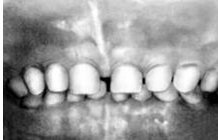

Рис 12. Молочные боковые резцы, адентия, 2 I 2